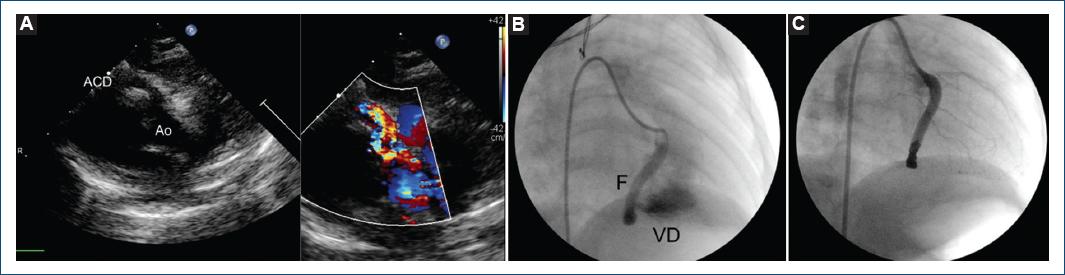

El segundo caso es otra niña de 4 meses, con peso de 7.2 kg, con presencia de soplo continuo paraesternal izquierdo alto y hallazgos ecocardiográficos de arteria coronaria derecha dilatada con un diámetro proximal de 5 mm (Z-score + 11.7 SD); distalmente se observó una fístula coronaria que drenaba al ventrículo derecho, inmediatamente por debajo de la valva posterior de la válvula tricúspide (Fig. 2 A). La angiografía coronaria mostró el tronco coronario derecho dilatado, con un trayecto fistuloso que drenaba al ventrículo derecho (Fig. 2 B). Se posicionó un catéter cobra visceral de 4 Fr en el ostium de la coronaria y se avanzó una guía de 0.14 × 180 CHOICE PT floppy hasta la parte distal de la fístula, y sobre esta con técnica coaxial se avanzó igualmente un microcatéter Excelsior SL 10, a través del cual se posicionaron dos coil Target 360 electrolargables de 6-20 mm y un coil de 5-15 mm (Boston Scientific/Scimed, Inc., Maple Grove, Minnesota, USA), logrando la oclusión completa de la porción terminal de la fístula (Fig. 2 C). La evolución fue satisfactoria y la paciente egresó a las 48 horas del procedimiento.

Figura 2 A: vista en el eje corto en bidimensional y Doppler color mostrando dilatación de la arteria coronaria derecha (ACD). B: angiografía en la que se aprecia una fístula coronaria derecha que llega al ventrículo derecho (VD). C: angiografía de control mostrando la oclusión completa distal de la fístula. AO: aorta; F: fístula.